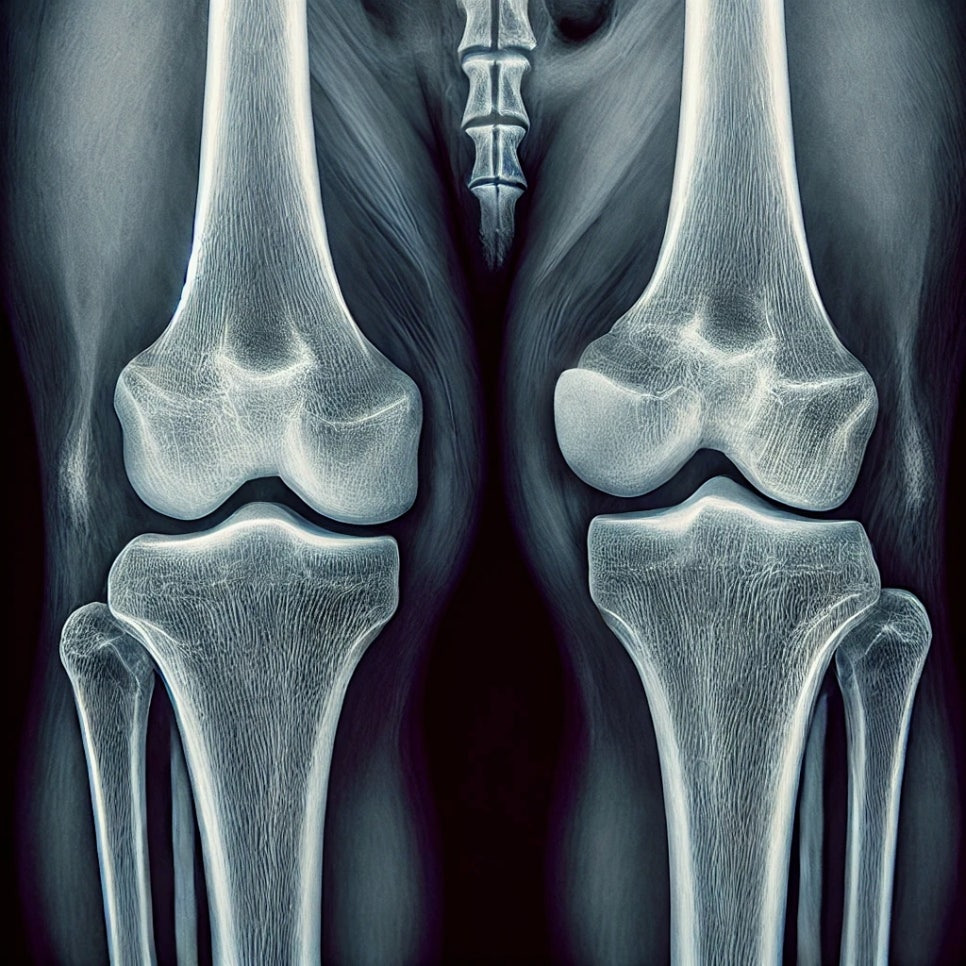

강아지 슬개골 탈구는 소형견에서 흔히 발생하는 질환으로, 무릎의 슬개골(무릎뼈)이 정상적인 위치에서 벗어나 탈구되는 것을 말합니다. 슬개골 탈구는 반려견의 활동성을 저하시키고, 적절한 치료가 이루어지지 않으면 만성적인 통증과 관절염으로 이어질 수 있습니다. 이번 포스팅에서는 강아지 슬개골 탈구 증상에 대해 알아보고, 그에 따른 대처 방법을 설명해 드리겠습니다.